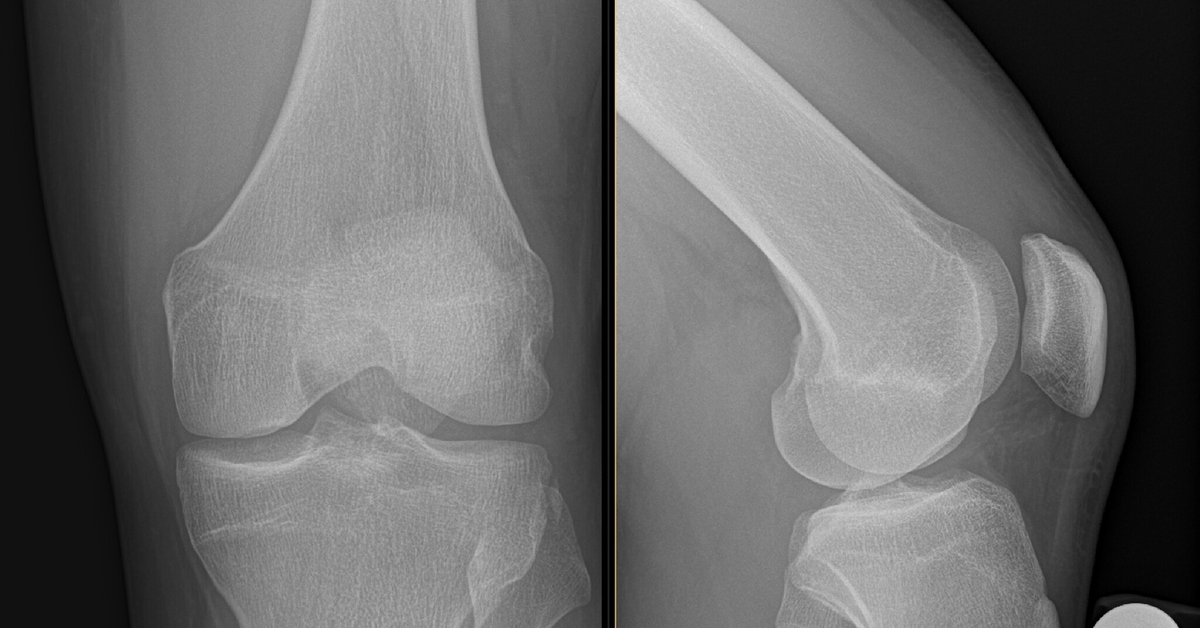

Рекурвация коленного сустава: рентгеновские снимки и объяснения